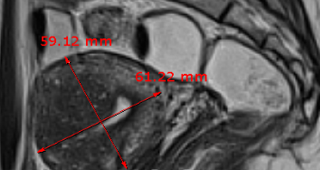

자궁근종 비수술 하이푸 치료 후 분만사례입니다. 자궁근종 하이푸 치료는 자궁근종 부위만 선택적으로 치료하는 시술로 자궁근종 전체적으로 시술하였습니다. 8cm 액화변성 자궁근종 하이푸 치료 시간은 57분이...